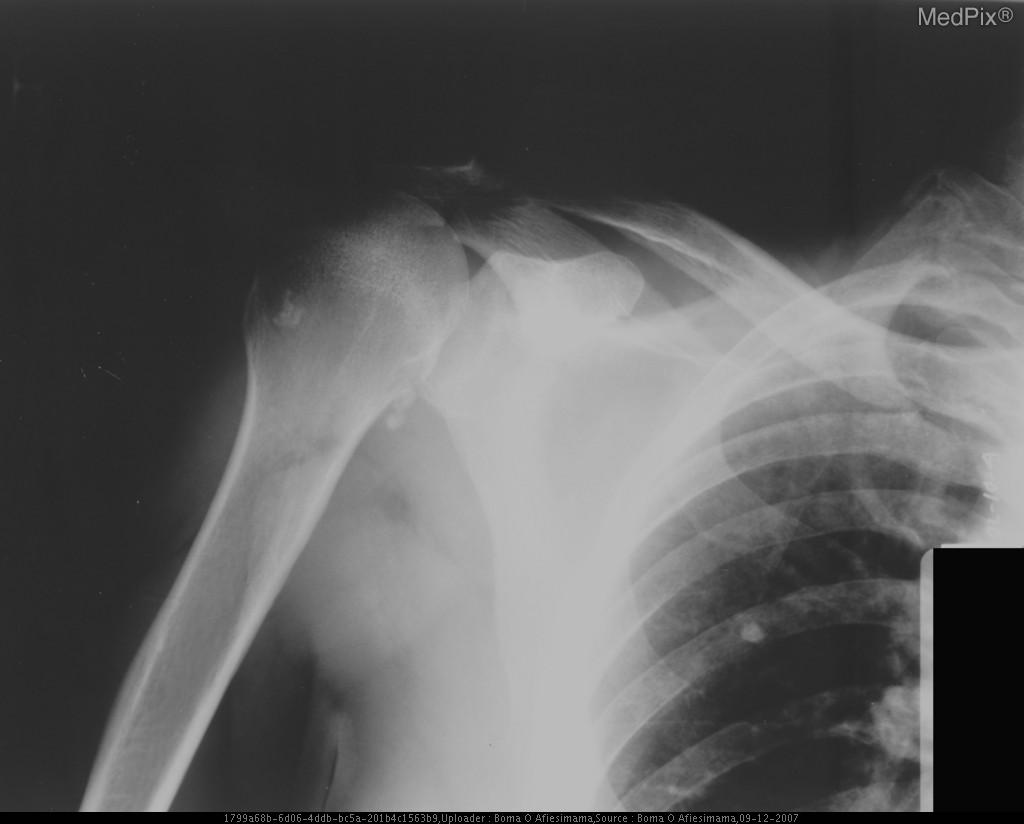

Акромион болит

Акромион болит 115 фотографий